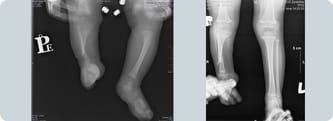

Operacja Wojtka odbyła się 14 stycznia 2015 r. Wszystko się udało! - Fixator jest troszkę wyżej niż było w planie.- pisze mama zza oceanu. - Stopkę udało się ustawić na prosto. A teraz wydłużanie, ściąganie w dół strzałki, która jest przerośnięta. Staw skokowy zrobiony :) Wojtek ma sześć śrub do kręcenia. Prawie codziennie wszystkie o 1 milimetr. Założeniem dr Paley'a jest wydłużenie nóżki o 4 cm.

Wojtek po operacji odczuwał duży ból i skurcze, nóżka mu spuchła. Krzyczał, że nie chce chodzić normalnie, tylko na kolankach. Nic dziwnego, to była poważna operacja, cały czas był na mocnych środkach przeciwbólowych, a i tak cierpiał. Podczas pierwszego spaceru łzy lały się strumieniami. Wszystko to minie, musi być tylko dzielny. Rehabilitacja pomaga, 24 stycznia Wojtek pierwszy raz stanął na własnych nóżkach! I w końcu miał swój pierwszy, własny, upragiony bucik, o którym tak marzył :) Wierzymy mocno, że Wojtek da radę mimo bólu, który jest dla niego nie do zniesienia.